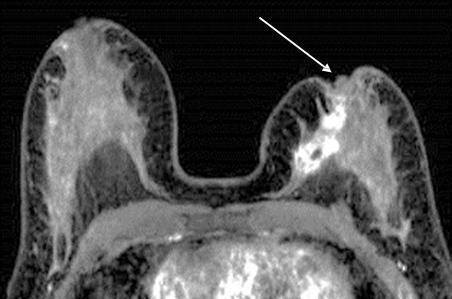

Инвазию опухоли в кожу оценивали по ее утолщению и изменению интенсивности МР-сигнала от нее (рис. 19).

Рисунок 19 — МР-маммография с контрастированием. Аксиальная плоскость. В левой МЖ отмечается указанное стрелкой локальное утолщение кожи и накопление КП, что указывает на инвазию.